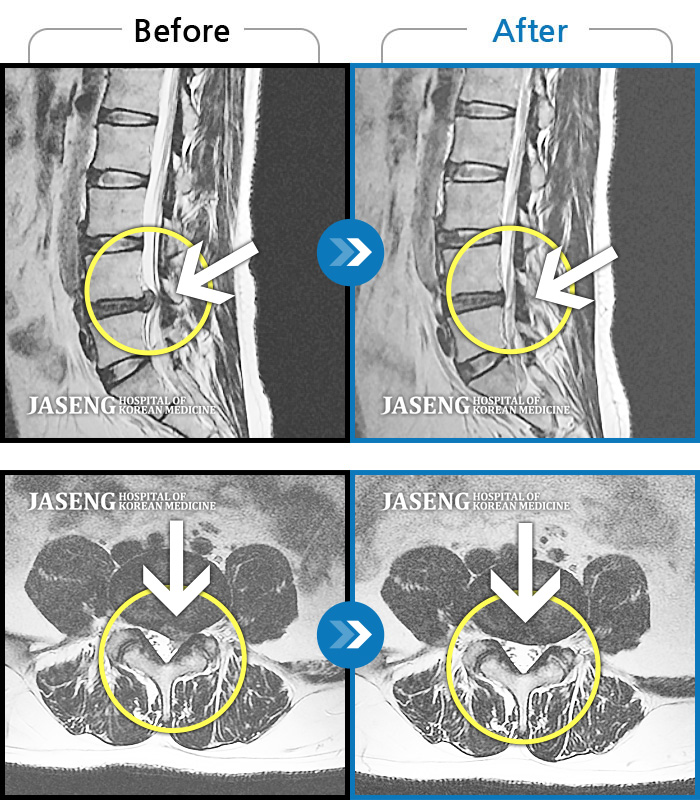

목디스크

부천 · 신동재 원장

운동 중 급격하게 발생한 후경부~좌측 어깨 및 좌측 상지 전반적인 저림이 있었다.

촬영시기

2021.10.26 ~ 2023.12.16

2024.01.05